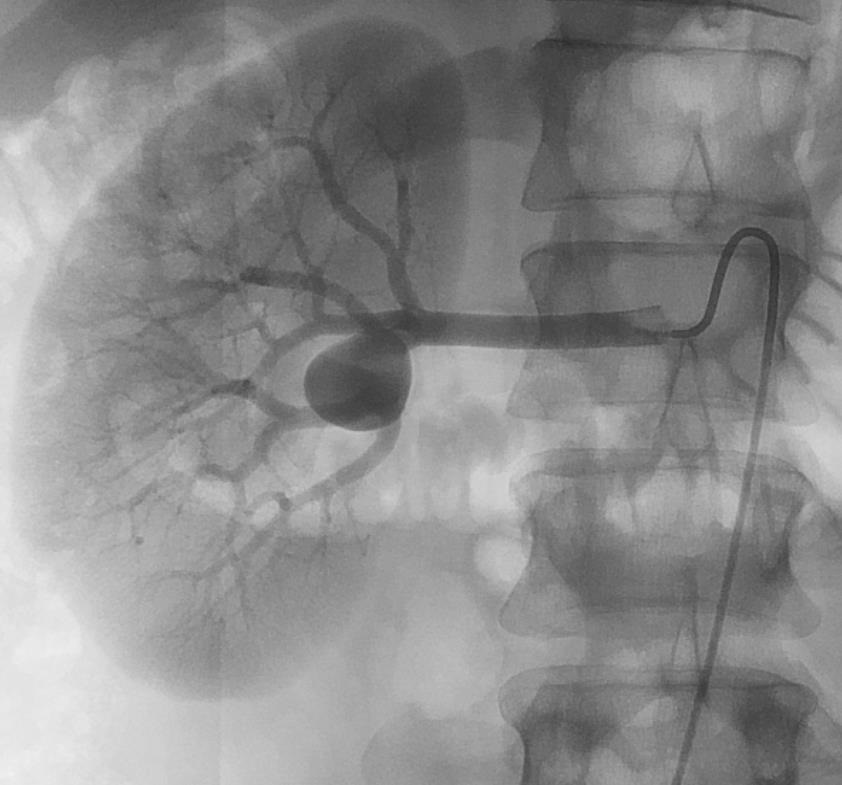

末端动脉阻塞(end-artery occlusion)

末端动脉栓塞:医源性肾损伤-移植肾活检

活检后动脉瘤破裂 |

微导管在载瘤动脉末端 |

载瘤动脉末端栓塞 |

Coil=3 |

直接动脉末端栓塞的过程是简单推出弹簧栓子(simply pushed out coil),但要求弹簧栓子的直径≥血管直径